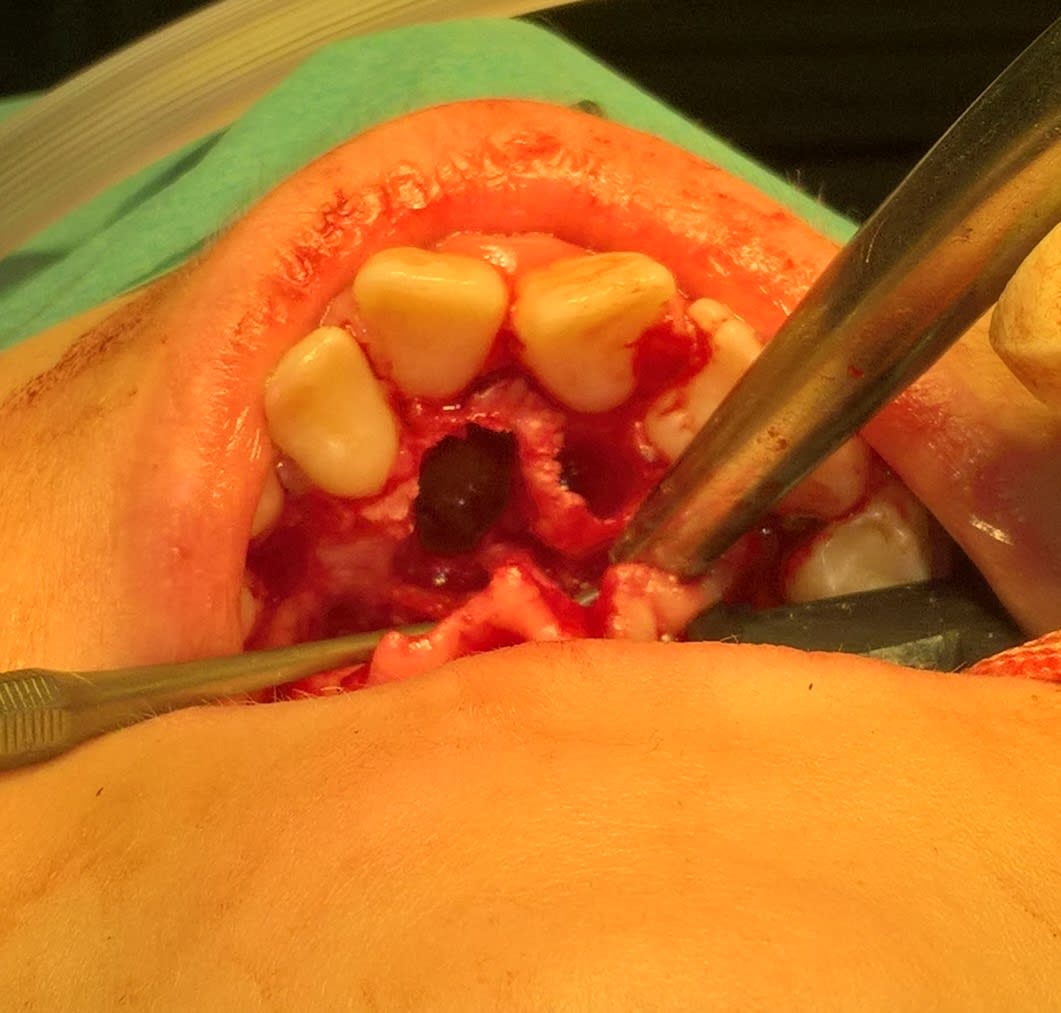

J'ai pu garder le paquet vasculo nerveux palatin antérieur. Les grincheux diront que çà sert à rien, mais j'avais le temps et je trouve çà classe :))

(le trou en palatin de la 21 c'était un odontoïde évolué en bouche que l'on ne voit pas bien sur les clichés)

Il est costaud le pédicule incisif (ça aurait sûrement saigné si tu avais dû le couper...).

Pour la 11bis tu l'as fragmentée ou juste ostéo+davier racine ?

Dernière question, c'est quoi la chaînette qui sort de la bouche ??

- pour les saignements, il y a la diathermie, ca aide bien...

- la chainette en métal, c est pas l attache de ta cale d ouverture pour pas risquer qu elle soit avalee par ton patient?

En fait j'ai cherché à trouver l'apex et comme j'avais déjà un bon dégagement en direction palatine j'ai juste eu à tirer dessus et la couronne n'a pas fait de résistance notable.

Effectivement la chaînette est accrochée à l'ouvre bouche